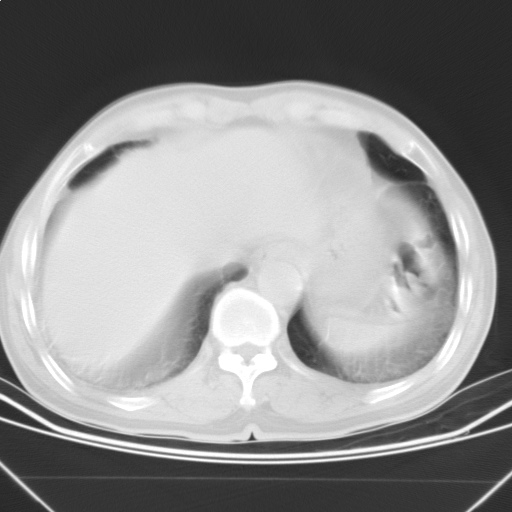

以下是引用随光逐影在2009-5-1 13:53:00的发言:[br]考虑为:1)两肺血行播散型肺结核;2)右肺下叶炎症感染。3)右侧胸膜增厚。